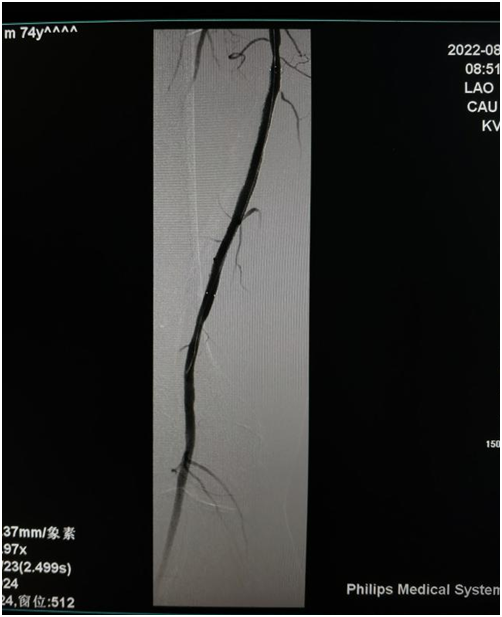

鞍钢总医院介入科主任任东铭教授及团队术前进行认真讨论并制定手术方案,术中顺利开通闭塞血管后,普通球囊扩张行血管准备,与病人家属充分沟通后,决定行药物洗脱支架置入术,手术顺利,支架置入后右下肢动脉血流恢复,术后症状明显好转。

△药物洗脱支架置入术后血流恢复